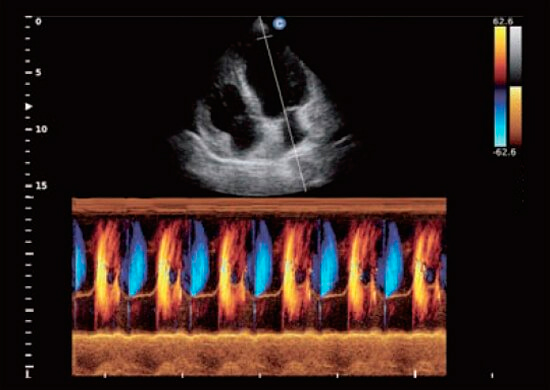

Mode mouvement couleur

- Fournit efficacement des informations sur le mouvement cardiaque.

- Affiche les informations correspondantes sur la direction du flux sanguin.

- Régurgitations faciles à détecter.